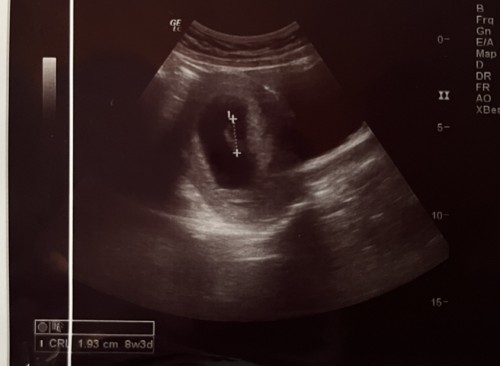

Mungkin ada bunda yg punya riwayat janin tidak berkembang, di kehamilan berikutnya seberapa sering kontrol / USG bun dan sebaiknya jarak berapa minggu untuk USG selanjutnya ? Saya ada riwayat janin tidak berkembang jadi ada sedikit kecemasan … saat ini alhamdulillah saya sedang mengandung usia 11 minggu. Sebaiknya kapan saya harus USG lagi ya bun ? terakhir usg usia 8 minggu alhamdulillah janin dan djj sudah ada dan kondisi normal. #ingintahu #pleasehelp #firstbaby

1 bulan yg lalu saya usg baru terlihat kantung janin dan dokter mengatakan itu normal, Kemarin saya usg ke dua, ketika di usg usia kandungan saya 8 week, tapi kalau dihitung dari hpht usia kandungan saya 12 week, usg terakhir janin sudah terlihat tapi tidak ada detak jantung dan dokter mengatakan janin tidak berkembang harus di kuret, sampai saat ini saya tidak ada flek,pendarahan,keram dll saya harus bagaimana ya bun? Karena saya benar benar cemas sekali ini kehamilan pertama saya… #ingintahu #pleasehelp